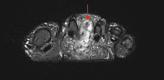

Phosphaturic mesenchymal tumors (PMT) are a rare neoplasm oftentimes associated with tumor-induced osteomalacia (TIO). The non-specific presentation and symptoms of these pathologies make them difficult to diagnose. We report a case of a 52-year-old patient with an intermetatarsal phosphaturic mesenchymal tumor who presented to the orthopedic sports medicine clinic with metabolic deficiencies and bilateral subtrochanteric cortical stress fractures indicative of osteomalacia. The tumor was entirely resected within nine months of symptom onset and has shown no recurrence at the one-year follow-up. This case report characterizes an unusual cause of stress fractures presenting to orthopedic sports medicine clinics and the variability in the presentation of phosphaturic mesenchymal tumors.